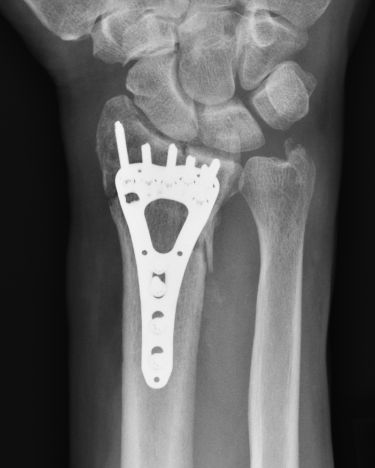

ORIF with locking plates

Advantages

Accurate restoration of intra-articular anatomy

Stable fixation with early mobilisation

Fragment specific plates

| Volar locking plates | Volar rim plates | Radial styloid plates |

Locking screws act as fixed angle devices Variable angle screws |

For very distal fracture fragments

Supplementary radial column fixation |

Volar locking plate technique

AO surgery modified Henry to distal forearm

Vumedi volar locking plate distal radius

Bed of FCR approach

- incision over FCR and mobilize ulnarly

- divide fascia in bed of FCR and retract radial artery laterally

- L shaped released of pronator quadratus

- cannot make volar capsulotomy - divides radiocarpal ligaments and causes instability

- elevate 1st extensor compartment (APL / EPB)

- release brachioradialis from radial styloid

Reduce fragments and temporarily stabilize with K wires

- apply volar plate with screw fixation in scaphoid and lunate fragments

- ensure not beyond watershed line to avoid flexor tendon irritation / rupture

- engage dorsal cortex but not too long to prevent EPL rupture

- on lateral, raise hand 30o to view joint

- +/- radial styloid plate if required